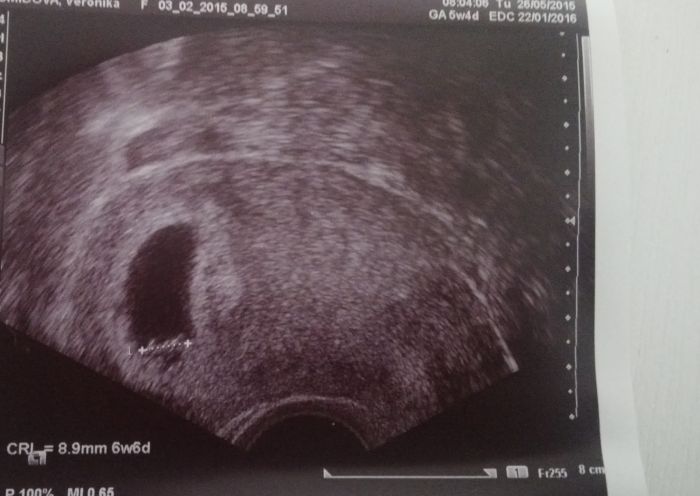

Ahojky holky, tak jsem dnes byla na kontrole u svého doktora a mám super zprávy! :) Jak všichni vite měla jsem jít včera na revizi,protoze v pátek jsem krvacela,v nemocnici odhadli gest.vek o 3 týdny Starší a ze neprospiva protože není srdíčko. Samozřejmě jsem nikam nešla. Dle PM jsem dnes 5+4, dle ultrazvuku 6+6 ale teď to hlavní. Jeho maminka dnes poprvé viděla a i slyšela jeho srdíčko!! Když jsem jela tramvaji domu museli si o mě myslet, že jsem blázen protože jsem se usmivala a tekly mi slzy jak hrachy :) Takže vám řeknu jedno: kdybych neměla prisnej klidovej režim půjdu té doktorce do nemocnice rozbit hubu! :-D Prikladam foto melo broucka :)